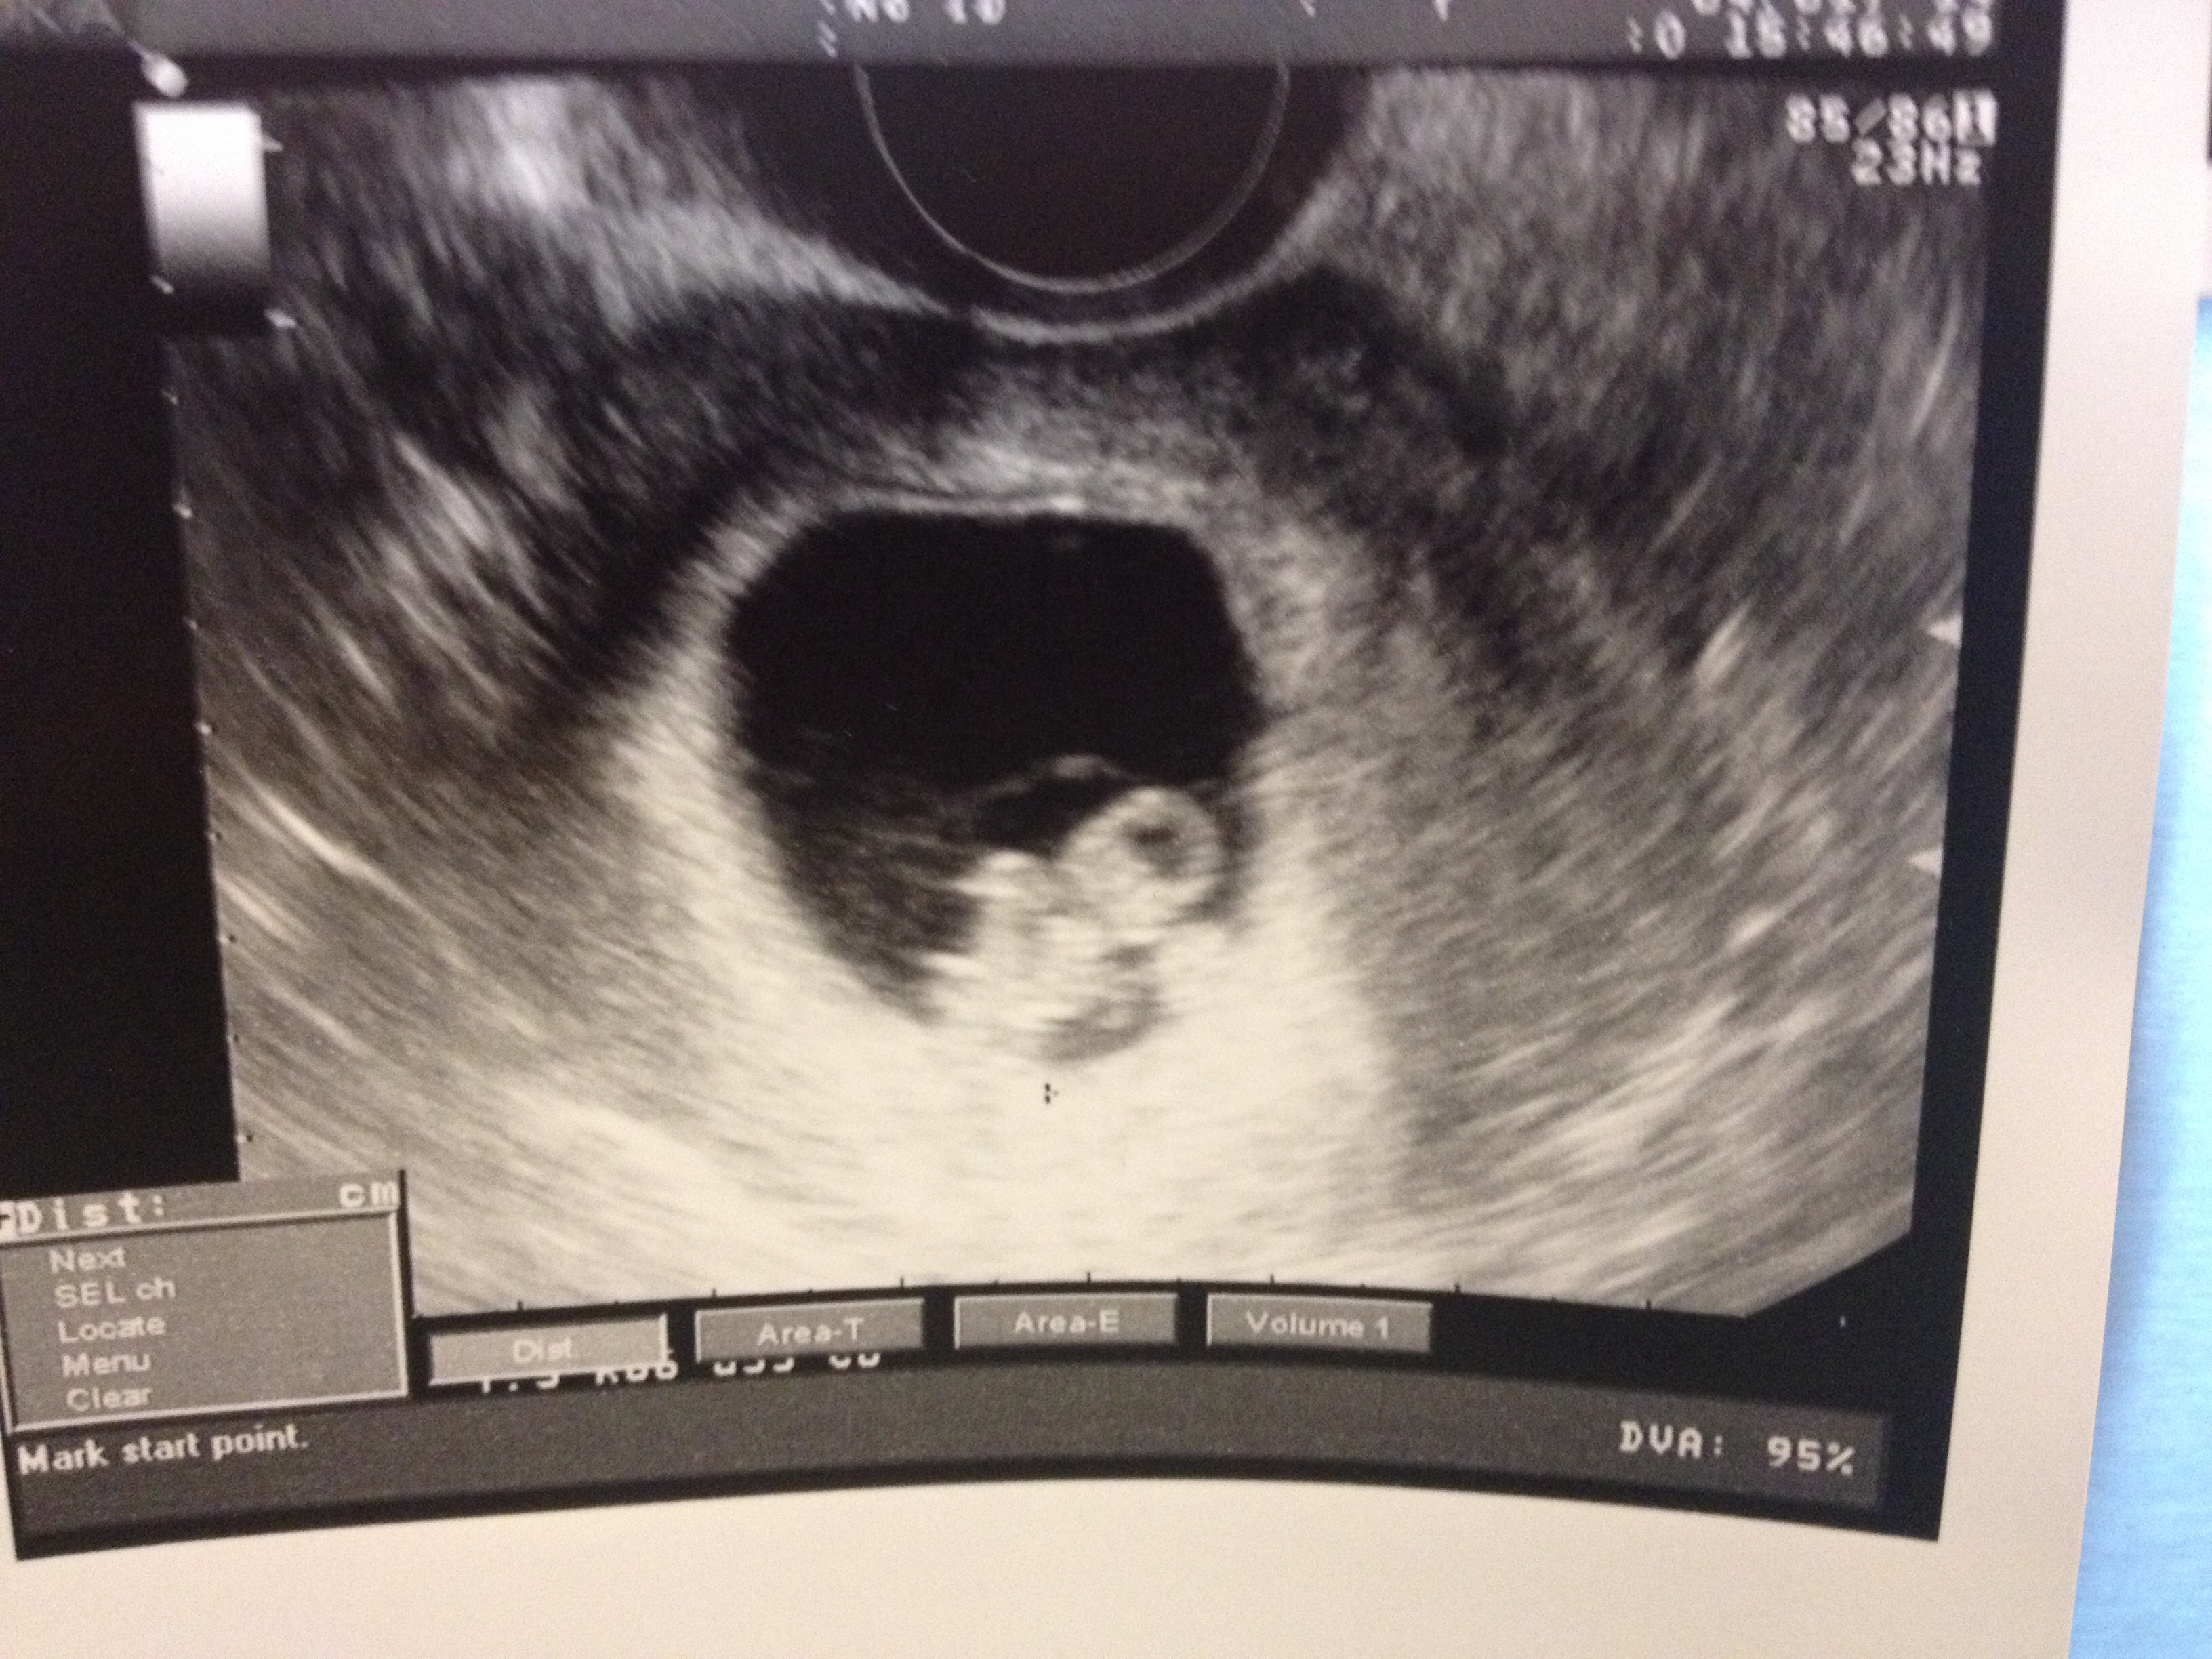

Here's my triangle looking baby.

ETA: I'm measuring right on time, HR was 153, and my EDD remains 11/11.

I've graduated to the OB and see the intake nurse on the 16th. Wooohoooo

Sorry for terrible picture quality.